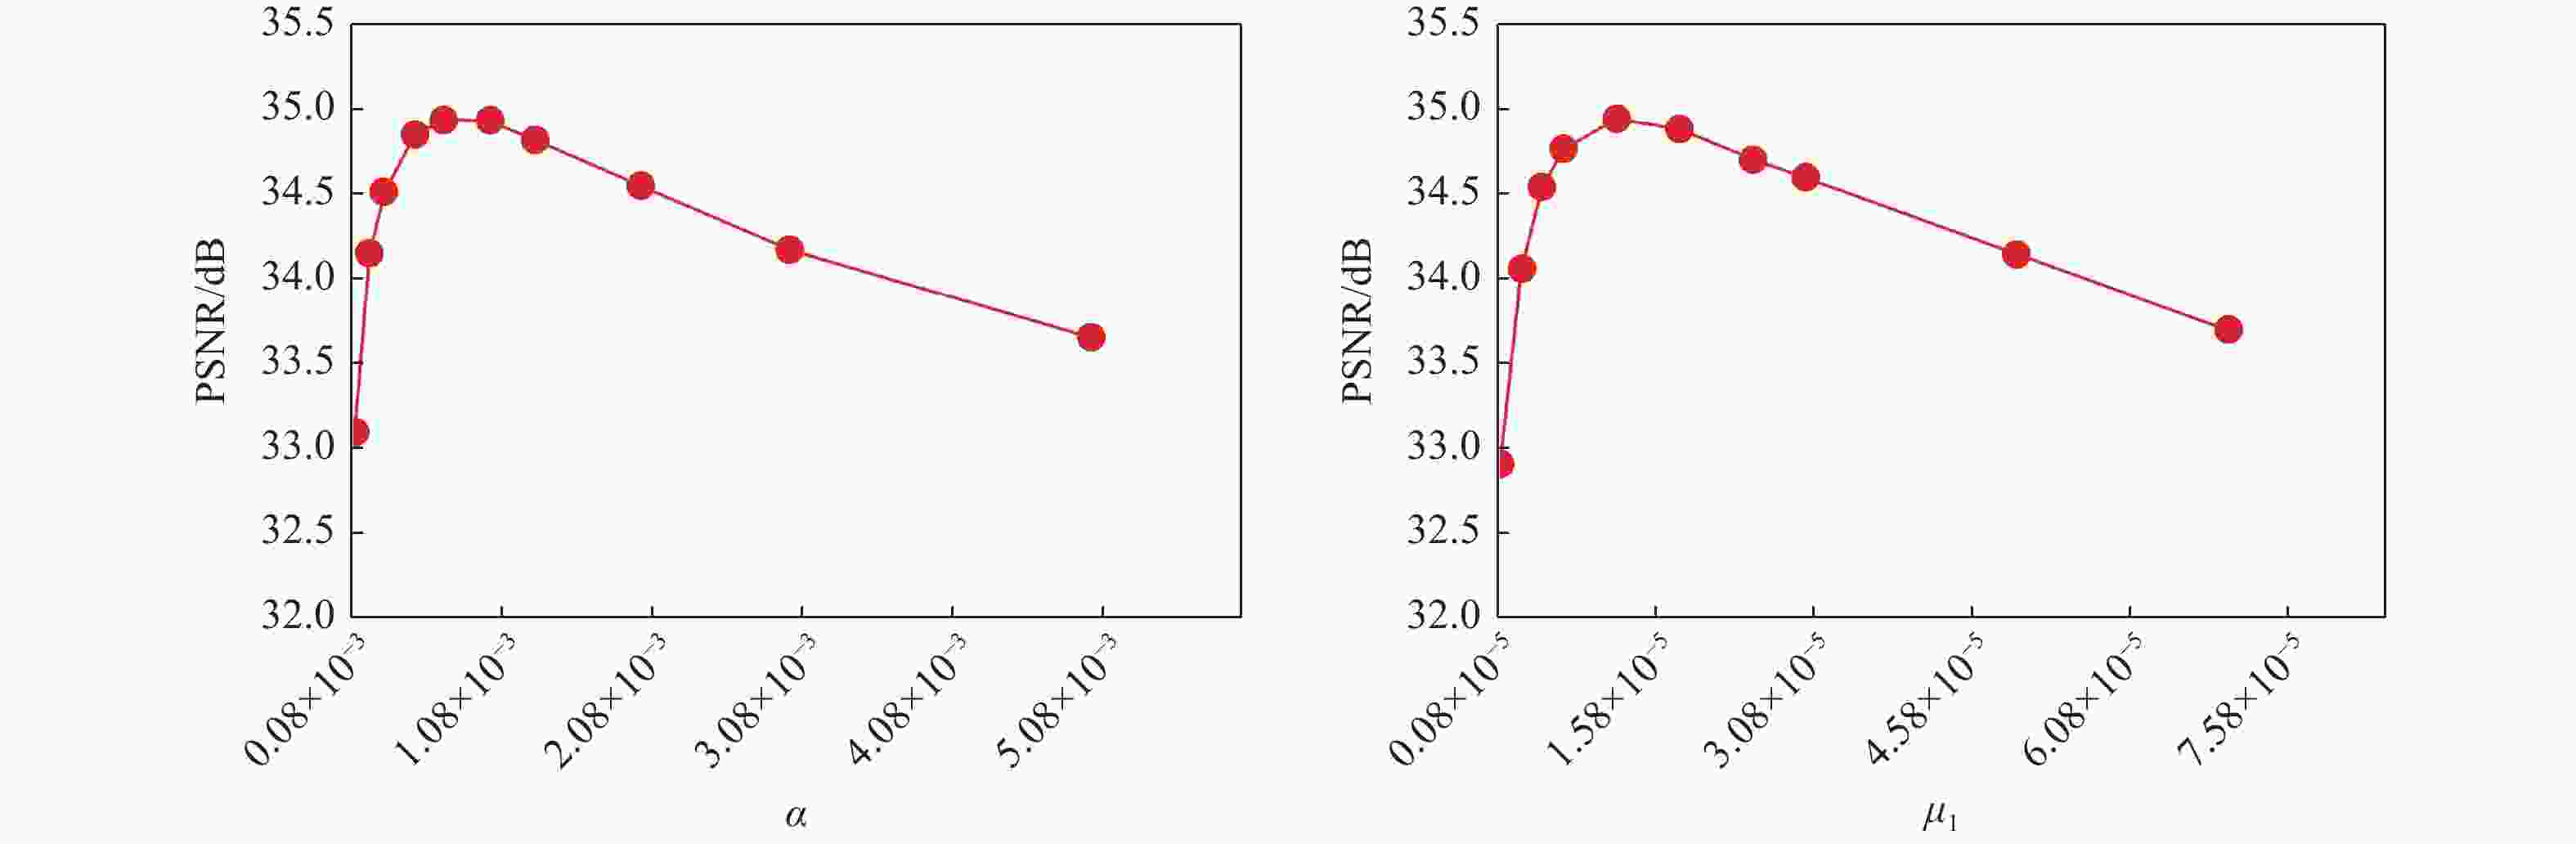

图 7 FMS-JTLHTC算法对5倍加速的1D-VRDU采样模式下dataset 1重建时参数$\alpha $和$ {\mu _1} $的变化对重构图像PSNR值的影响

Figure 7. Effect of variation of parameters $\alpha $ and $ {\mu _1} $ on PSNR values of reconstructed images during dataset 1 reconstruction by FMS-JTLHTC algorithm for 1D-VRDU sampling mode with 5-fold acceleration